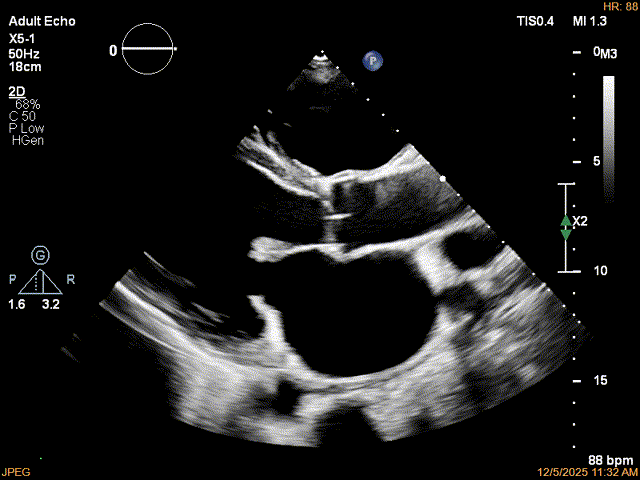

患者食道胃底静脉曲张,遂行TTE术前评估

术前TTE评估:

MR反流病因:DMR(部分腱索断裂)、Carpentier II型;

反流程度:极重度(5+),PISA法估测EROA约1.12cm²,R-VOL约98ml;

病变情况:P2-部分P3,脱垂宽度约27mm ,连枷间距11-13mm,瓣口面积7.8cm²,PML约25mm

其他:TR(重度) ,间接估测PASP约65mmHg;

预估手术难点:后叶冗长,脱垂宽度大,连枷间距大。